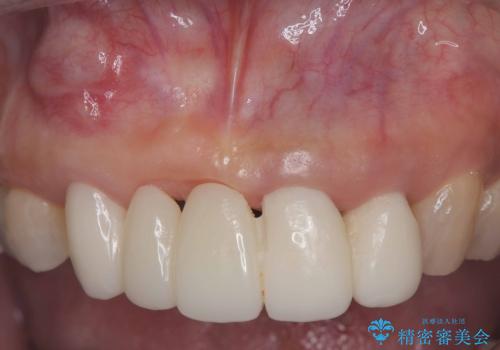

- 歯茎の大きな腫れを主訴に来院された患者様です。前歯5本にはブリッジが装着されていました。レントゲン検査より、右上3番に大きな根尖病巣が認められ、さらに左上1、2番の支台歯にも破折があったため、抜歯を行いました。その後、インプラントを3本埋入し、オールセラミッククラウンのブリッジで補綴しました。

術前のCT画像より、抜歯即時インプラントが可能と判断したため、抜歯と同時にインプラント埋入を行いました。術式にはセミルーナーフラップを用い、唇側の骨吸収を抑える目的でルートメンブレンテクニックを併用しました。